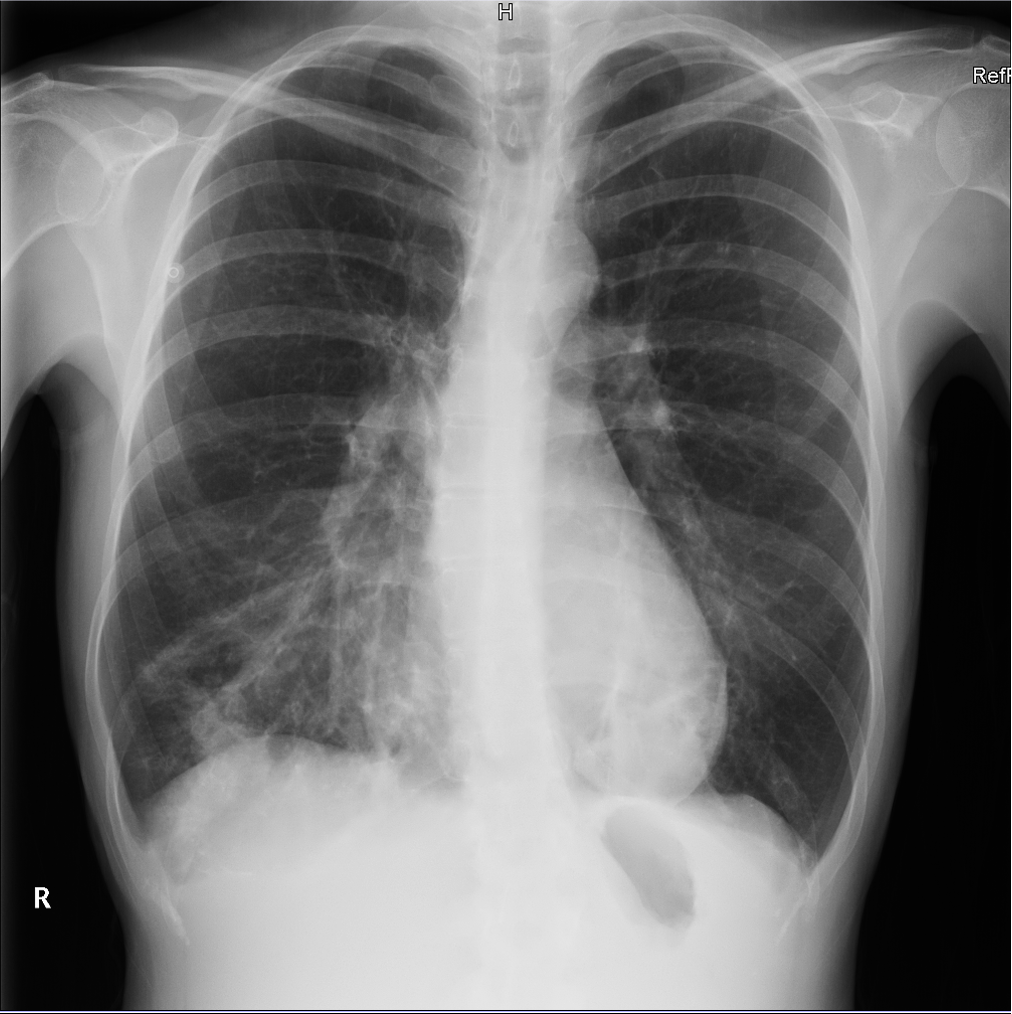

Mujer de 43 años, asma bronquial en tratamiento con broncodilatadores a demanda, acude por síntomas catarrales de 7 días de evolución, con empeoramiento progresivo con aparición de expectoración purulenta y pico febril en las últimas 24 horas, así como dolor pleuromecánico en hemitórax derecho, con disnea de esfuerzos. Normotensa, taquicárdica, afebril a su valoración y con saturación 95% basal. A la auscultación, crepitantes en base derecha. Analíticamente leve leucocitosis con neutrofilia y elevación de PCR (130,5 mg/L). Se realiza un electrocardiograma, que muestra una taquicardia sinusal, en otros; y una radiografía de tórax, en la que se aprecia un infiltrado en base derecha, sin derrame aparente.

Se completa estudio con ecografía pulmonar a pie de cama, que muestra Sliding conservado, con patrón de líneas B en base y campo medio derecho, con una pequeña consolidación subpleural en base derecha. En base izquierda, consolidación pulmonar, con hepatización, y derrame pleural asociado.

La ecografía pulmonar nos proporcionó hallazgos que no eran visibles en la radiografía simple, permitiendo una mejor clasificación de la severidad del cuadro de la paciente, adaptando la actitud clínica según los protocolos existentes.